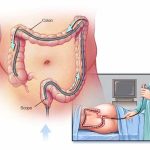

سونوگرافی رحم و تخمدان، که گاهی با نامهای سونوگرافی لگن یا سونوگرافی بارداری نیز شناخته میشود، روشی تصویربرداری است که با استفاده از امواج صوتی، تصاویر دقیق از اجزای داخلی لگن ارائه میدهد. این روش غیرتهاجمی و بدون درد، بدون استفاده از اشعه مضر، اطلاعات مهمی در اختیار پزشکان قرار میدهد و به تشخیص زودهنگام بسیاری از مشکلات سلامت زنان کمک میکند.

سونوگرافی رحم و تخمدان برای بررسی سرویکس (دهانه رحم)، لولههای فالوپ، تخمدانها، رحم و واژن به کار میرود و بسته به هدف انجام آن، انواع مختلفی دارد:

- سونوگرافی شکمی: اندامهای داخلی لگن را از طریق دیواره شکم بررسی میکند.

- سونوگرافی ترانسواژینال: از طریق واژن انجام میشود و تصاویر دقیقی از رحم و تخمدانها ارائه میدهد.

نحوه انجام سونوگرافی رحم و تخمدان

سونوگرافی با استفاده از دستگاهی به نام ترانسدیوسر (مبدل) انجام میشود. این دستگاه امواج صوتی با فرکانس بسیار بالا و غیرقابلشنیدن برای گوش انسان تولید میکند. مبدل روی پوست قرار میگیرد و امواج صوتی از طریق بافتها به اندامها و ساختارهای داخلی بدن منتقل میشوند. سپس این امواج پس از بازتاب از اندامها دوباره توسط مبدل دریافت شده و رایانه متصل به دستگاه آنها را به تصاویر واقعی از اندامها و بافتهای داخلی تبدیل میکند.

سونوگرافی رحم و تخمدان به دو روش انجام میشود:

- سونوگرافی شکمی (ترانسآبدومینال): مبدل روی سطح شکم قرار میگیرد و با کمک ژل مخصوص تصاویر از روی پوست گرفته میشود.

- سونوگرافی واژینال (ترانسواژینال): مبدل باریک و بلند با پوشش لاتکس و ژل روانکننده بهآرامی وارد واژن میشود تا تصاویر دقیقتر و واضحتری از رحم و تخمدانها به دست آید.

سونوگرافی شکمی رحم و تخمدان چگونه انجام میشود؟

سونوگرافی شکمی از طریق سطح شکم انجام میشود. فرد به پشت روی تخت معاینه دراز میکشد و تکنسین مقدار کمی ژل مخصوص روی مبدل میزند. این ژل باعث حرکت راحتتر مبدل روی پوست، جلوگیری از ورود هوا بین دستگاه و پوست و افزایش کیفیت تصاویر میشود. سپس مبدل بهآرامی روی پوست شکم حرکت داده میشود. این روش کاملاً بدون درد است و معمولاً برای بررسیهای کلی اندامهای لگن بهکار میرود.

سونوگرافی واژینال رحم و تخمدان چگونه انجام میشود؟

سونوگرافی ترانسواژینال از طریق واژن انجام میشود. در این روش، مبدل با ژل روانکننده و پوششی محافظ پوشانده شده و چند سانتیمتر وارد واژن میشود. این نوع سونوگرافی ممکن است کمی احساس فشار یا ناراحتی ایجاد کند، اما معمولاً دردناک نیست. پزشک با حرکت دادن مبدل در زوایای مختلف، تصاویر دقیق و واضحی از رحم، تخمدانها و بافتهای اطراف بهدست میآورد.